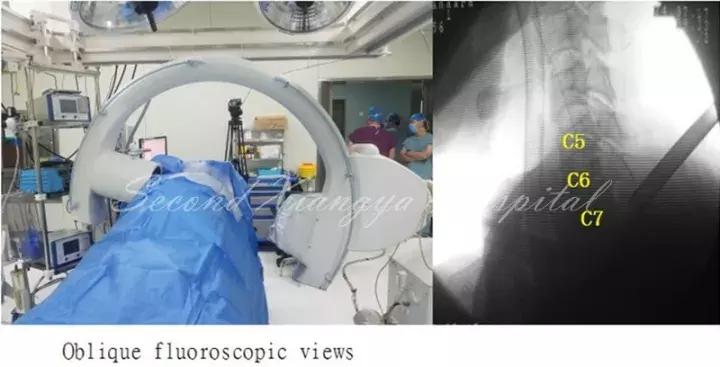

颈椎前路:与腰椎相比,颈椎由于毗邻结构复杂,穿刺风险相对较高,尤其在前路进行经皮内镜手术时更为明显。鉴于在颈椎开展经皮内镜脊髓神经损伤“零容忍”,穿刺时应特别注意技巧,即“气管投影,两指技术,皮触骨面,侧透避深。”术中透视时需找到气管侧方投影位置,然后用中指和无名指将血管鞘和内脏鞘推挤开,直至皮肤触及骨面,在两指之间穿刺入椎间隙后需透视证实未进入椎管,以确保脊髓安全。

颈椎后路锁孔:颈椎后路结构单一,穿刺的靶点指向病变节段上椎板下缘、关节突和下椎板上缘组成的“V”点偏外骨性结构,穿刺端避免偏内落入椎管误伤脊髓。

同时,侧位透视时应调整C-Arm角度,也可通过C臂聚焦来显露被肩胛骨遮挡的下颈椎区域,从而帮助准确定位手术节段和防止穿刺后工作套管置入过深。